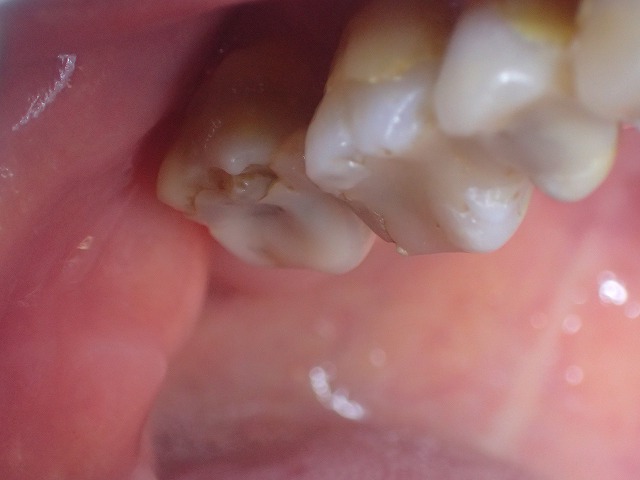

レジン充填が崩壊 その後、奥歯が崩れてきたので、ジルコニアクラウン

強度もあり、アレルギーもなし美しく信頼の材料

レジン充填が崩れてきました。

レジン充填が何度もされており

このままでは大きく崩れるリスクがあります。

大きい奥歯(大臼歯)には

レジン充填やキャドカム冠は

なるべくやらないほうが無難です。

強度不足なので、崩れて虫歯になったり

摩耗したりと短寿命です。

ジルコニアクラン制作

大臼歯のジルコニアクラウン装着